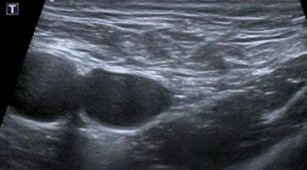

Test du valsalva

Hernie fémorale